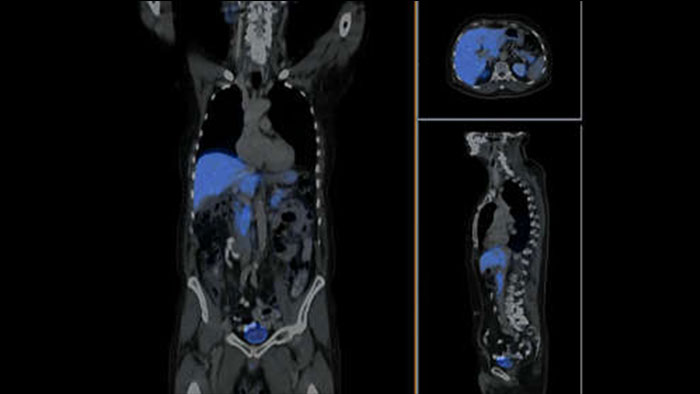

Ocena przydatności cyfrowej tomografii PET/CT

Posłuchaj opinii kolegów z branży o zmieniających się technologiach PET/CT i o tym, jak cyfrowe tomografy PET/CT mogą pomóc poprawić jakość opieki medycznej.

Szybsze badania i korzystne zmiany dzięki tomografowi Vereos PET/CT

Dowiedz się, jak doktor Michael V. Knopp, dzięki skanerowi Vereos PET/CT z opatentowaną technologią detektora cyfrowego zliczania fotonów, uzyskuje obrazy wysokiej jakości przy niskich dawkach i krótkich czasach akwizycji.